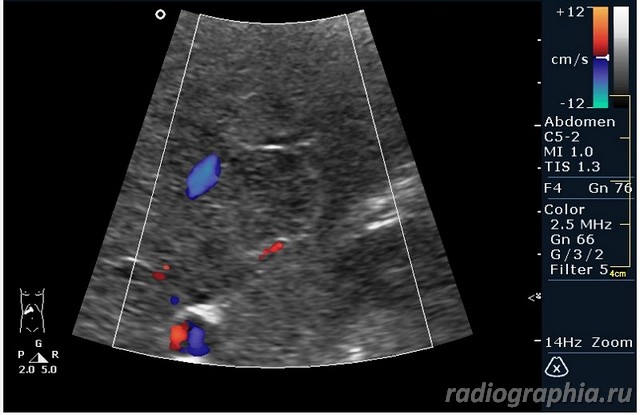

гемангиома,рядом питающий сосуд

Мне тоже нравится версия, что это - гемангиома.Нелли писал(а):гемангиома,рядом питающий сосуд